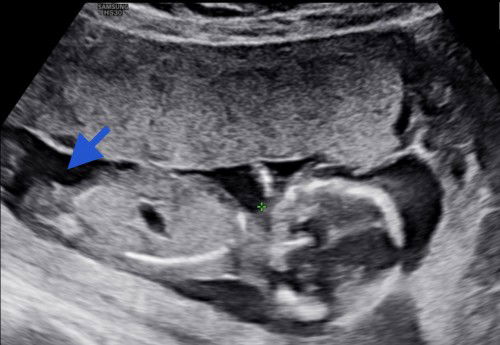

Assalam ibu2,nie gmbr mse scan 16w. Yg kt tnda biru tue bebird baby ke paha dia ye? Ad scan jantina,tp xnmpk. Skrg dh 18w. Ingt nk tnggu 20w lbh nnti br scan lg jantina. Jgn kecam ye 🤗